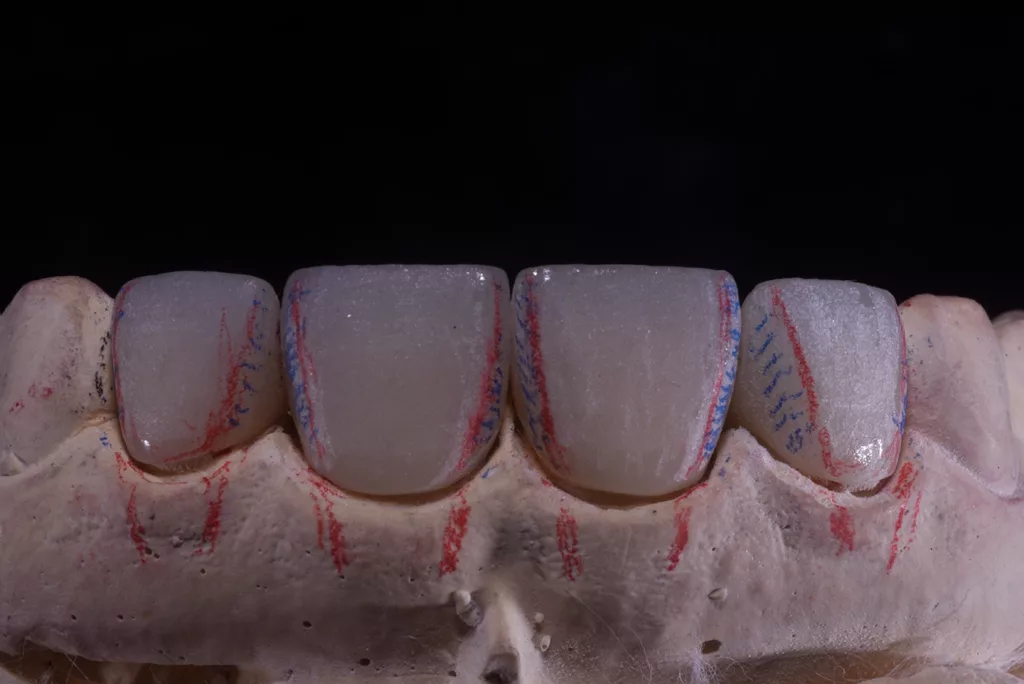

Die Kronen wurden in diesem Fall aus dem Material IPS e.max® ZirCAD Prime Esthetic von Ivoclar angefertigt. Die Transparenz des gewählten Zirkoniumdioxids ermöglichte die Fertigung dünner Kronen von 0,5 mm und gleichzeitig eine präzise Farbreproduktion ohne dicke Schichtung. Das Stumpfdesign wurde so gewählt, dass das Zirkoniumdioxid bis zur Inzisalkante reichte, um Schneidekantenfrakturen zu vermeiden. Die Schichtung erfolgte durch Auftragen von IPS e.max® Ceram Dentin-Pulver (OE1, OE2 und T1) auf das Grundgerüst (Abb. 57 bis 63).